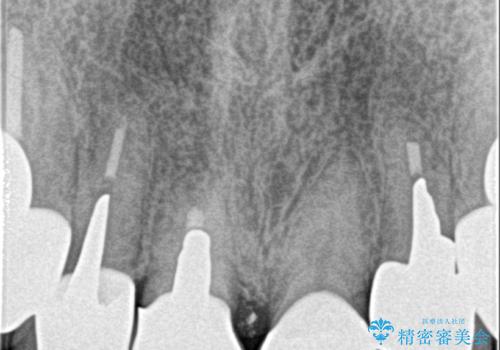

10数年前に治療を行った保険適応の硬質レジン前装冠は変色劣化が進み、審美的に問題があるだけでなく虫歯のリスクも高くなり好ましくない状況です。

審美的かつ精度の高いセラミック治療を行うことで、汚れがつきにくく虫歯や歯周病の感染リスクを将来にわたって抑える治療が可能になります。